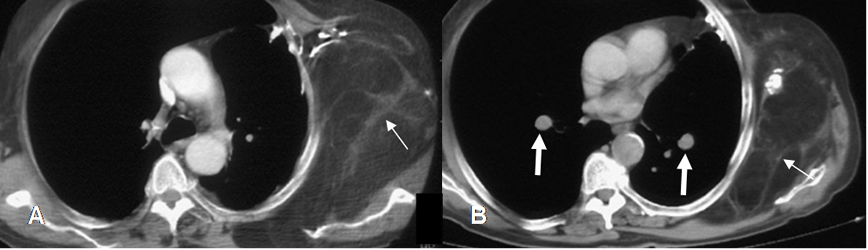

Fig 173. Liposarcoma.

A y B: TAC axial. Prominencia asimétrica de los tejidos blandos en la pared costal izquierda. Muestra septos fibrosos gruesos y calcificación, correspondiendo a liposarcoma. (Flechas delgadas). En B hay nódulos pulmonares, por enfermedad metastásica. (Flechas gruesas).